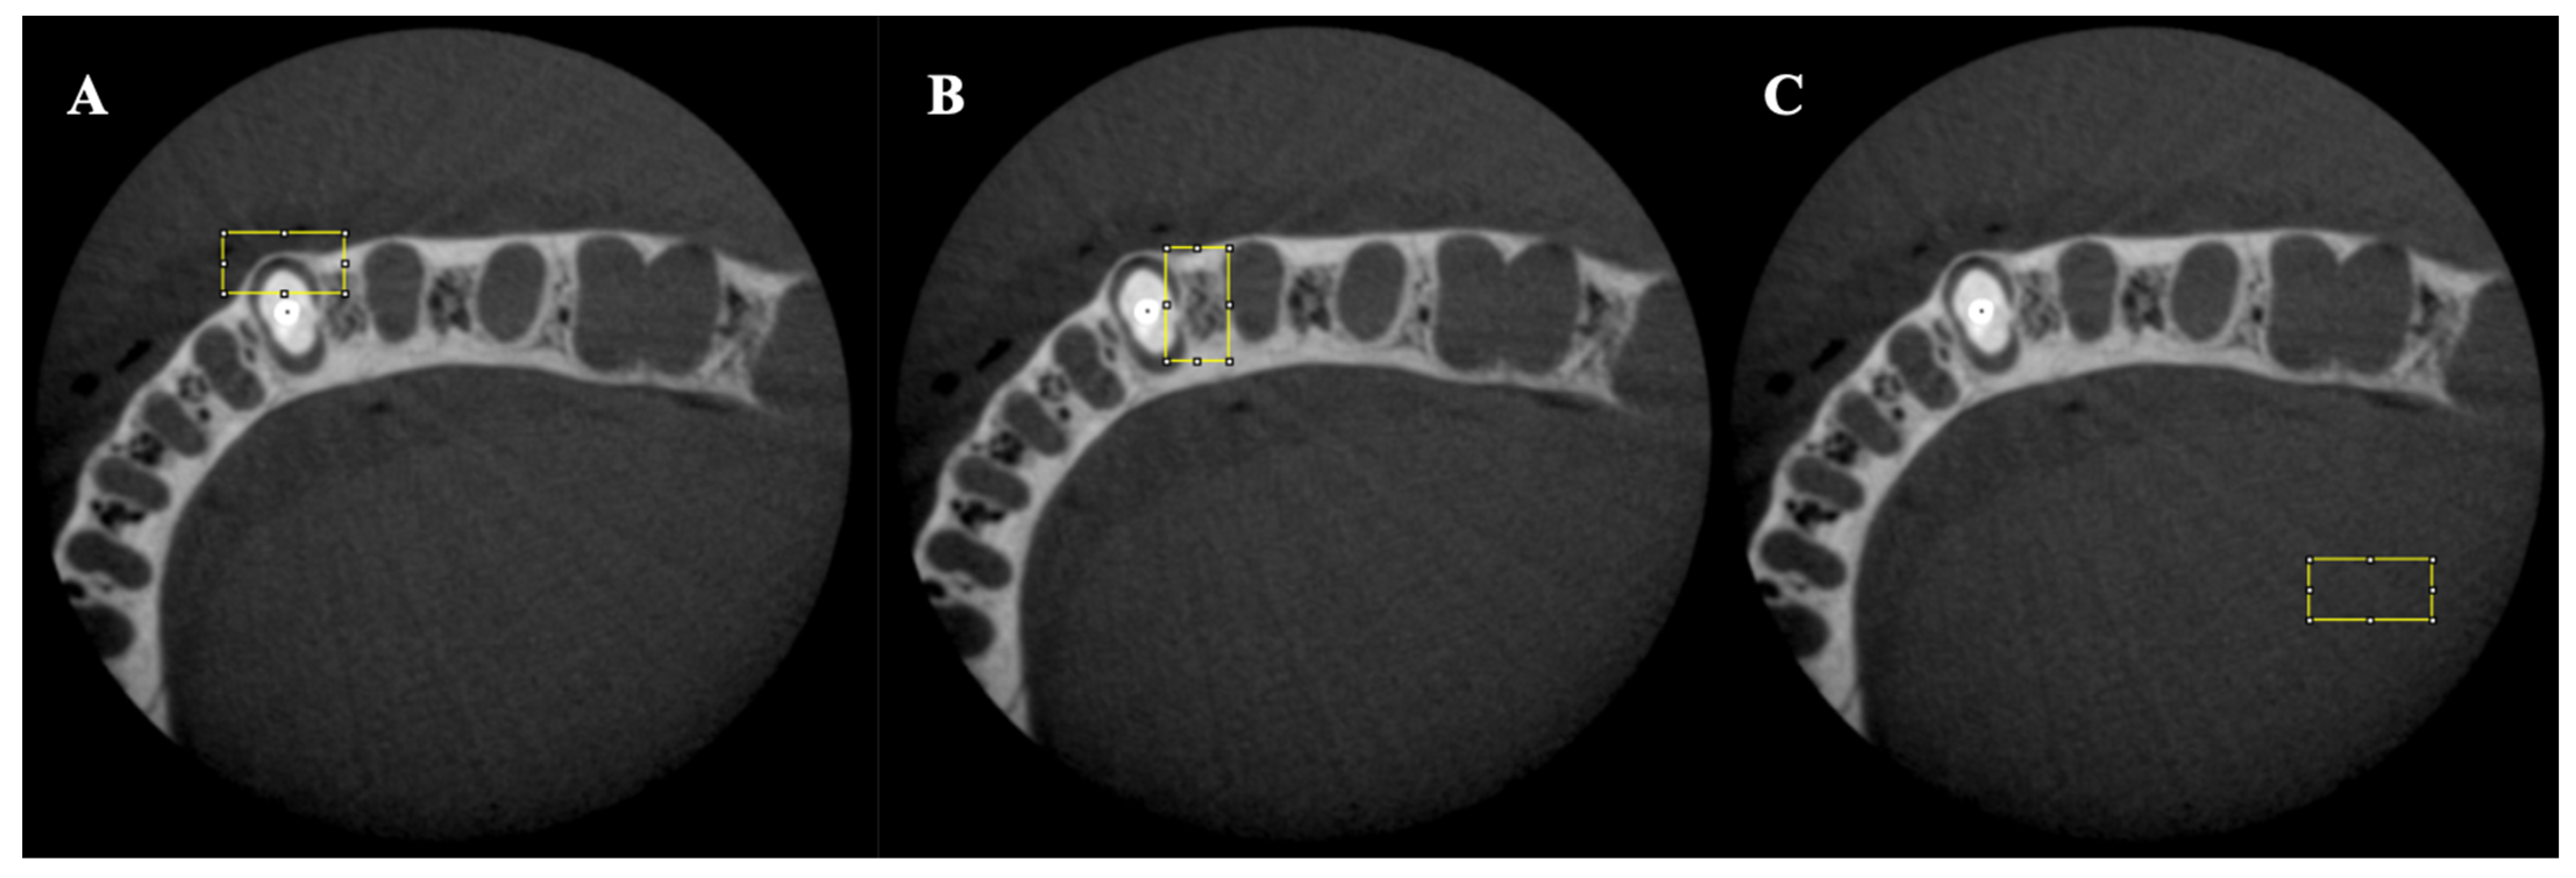

A total of 480 CBCT scans were acquired using multi-slice digital imaging in communications in medicine (DICOM) format with 0.16 mm thickness. For each volume, two slices were selected at 2 and 4 mm from the cementoenamel junction (CEJ), representing the cervical and middle root thirds (Figure 2).

The analysis was performed using ImageJ software (National Institutes of Health, Bethesda, MD, USA). In each image, three areas were selected, and, for each area, the minimum, maximum, and mean gray values, as well as the standard deviation, were calculated. The first area was chosen as a rectangle (width 60 × height 30) in the buccal region of the root except for the post material. The second rectangular area (width 30 × height 60) was chosen in the interproximal area excluding the post material. Lastly, the third rectangular area (width 60 × height 30) was chosen as a control area away from the tooth and artifact toward the farthest edge of the volume for each slice (Figure 3). The rectangular areas included the straight lines of steaking artifacts and beam-hardening dark bands.

Figure 3. Area of interest for each middle and cervical third: (A) buccal area (width 60 × height 30); (B) interproximal area (width 30 × height 60); (C) control area (width 60 × height 30).